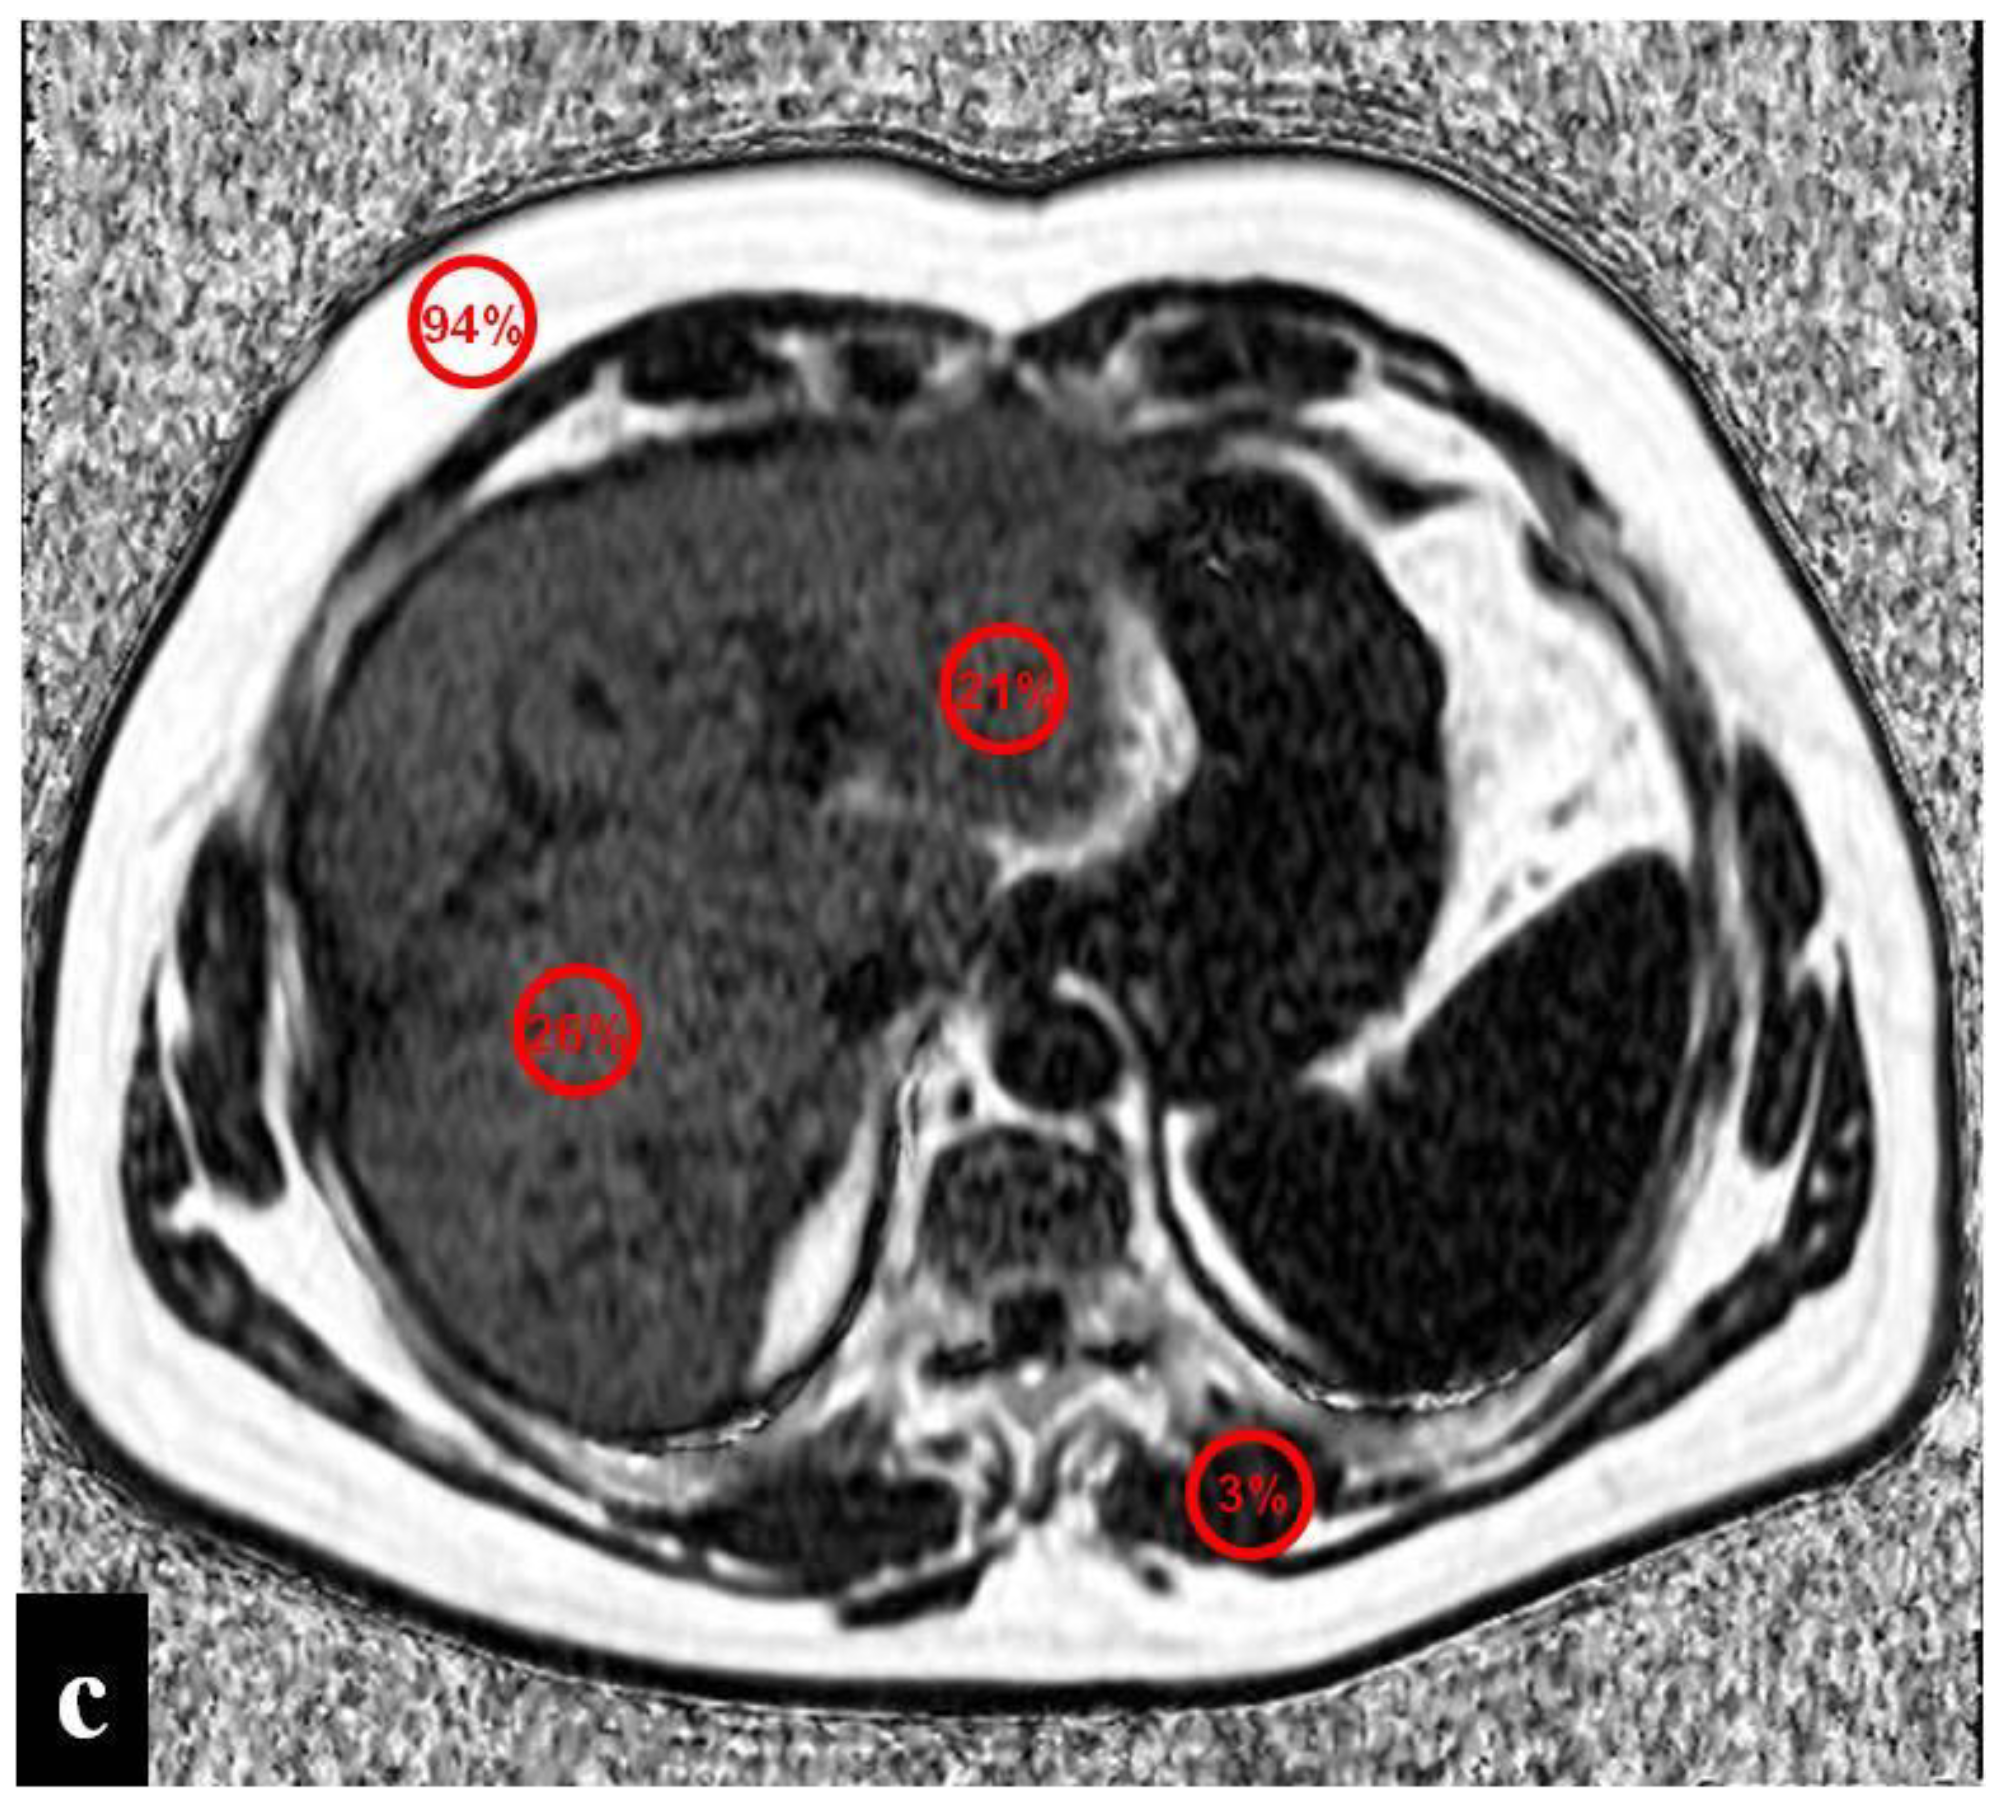

Figure 3.

(a–d) A 55-year-old man with hepatic metastases from rectal cancer undergoing neo-adjuvant chemotherapy with folinic acid, 5-fluorouracil, and oxaliplatin (FOLFOX). After chemotherapy, in the same plane as metastasis of the left lobe (red arrow), a small focal lesion developed in segment 6 (white arrow). The lesion was hyperintense in the T2-weighted image (a) and presented a slight restriction in the DW-MRI image, with b-values of 1000 s/mm2 (b). The arterial phase (c) of the Gd-EOB-DTPA-enhanced MR image demonstrated homogeneous and strong enhancement at the level of the lesion, which presented a doughnut-like enhancement with hyperintense periphery and a hypointense center in the hepatobiliary phase image (d). The findings are consistent with an FNH-like lesion. In the hepatobiliary phase image (d), the patchy heterogeneity of the surrounding hepatic parenchyma, with reticular enhancement and scattering of hypodense areas, is also appreciably suggestive of SOS.